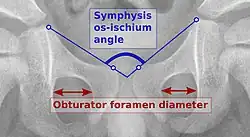

Reliability of measurements increases if indicators of pelvic alignment are taken into account:

- Obturator foramen diameter ratio (of Tönnis): A quotient of pelvic rotation by dividing the horizontal diameter of the obturator foramen of the right side and that of the left. In neutral rotation the ratio is 1 but is considered to be acceptable when it is between 0.56 and 1.8.[3]

- Symphysis os-ischium angle (of Tönnis): This evaluates the pelvic position in the sagittal plane. Lines are drawn from the highest point of the ischium to the most prominent point of the symphysis, joining at the inside of the pelvis. The range of normal values is from 90 to 135° and is related to the infant’s age.[3]